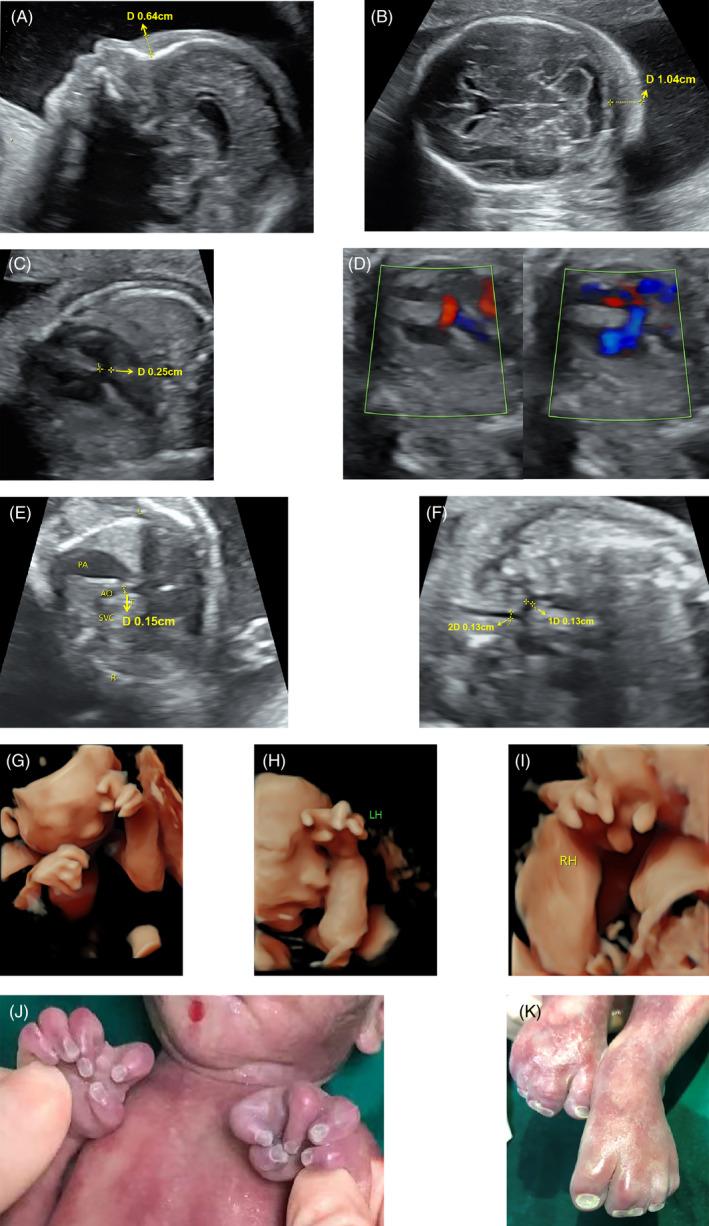

The fetus presented a previously unreported interstitial deletion of 2q24.3-q32.1. WES and CNV-seq revealed a de novo 18.46 Mb deletion at 2q24.3-q32.1, a region involving 94 protein-coding genes, including HOXD13, MAP3K20, DLX1, DLX2, SCN2A, and SCN1A. The fetus had upper and lower limb malformations, including camptodactyly and syndactyly, along with congenital cardiac defects.

Herein, we report a fetus with a novel microdeletion of chromosome 2q24.3-q32.1, likely a heterozygous pathogenic variant. Haploinsufficiency of HOXD13 might be related to limb deformity in the fetus.

胎儿呈现出一种以前未报道过的 2q24.3-q32.1 中间缺失。WES 和 CNV-seq 揭示了胎儿 2q24.3-q32.1 上的一个新发的 18.46 Mb 缺失,该区域包含 94 个编码蛋白的基因,包括 HOXD13、MAP3K20、DLX1、DLX2、SCN2A 和 SCN1A。胎儿存在上肢和下肢畸形,包括掌挛缩和并指畸形,以及先天性心脏缺陷。

在此,我们报告了一例染色体 2q24.3-q32.1 新型微缺失的胎儿,可能是杂合致病性变异。HOXD13 的单倍不足可能与胎儿肢体畸形有关。